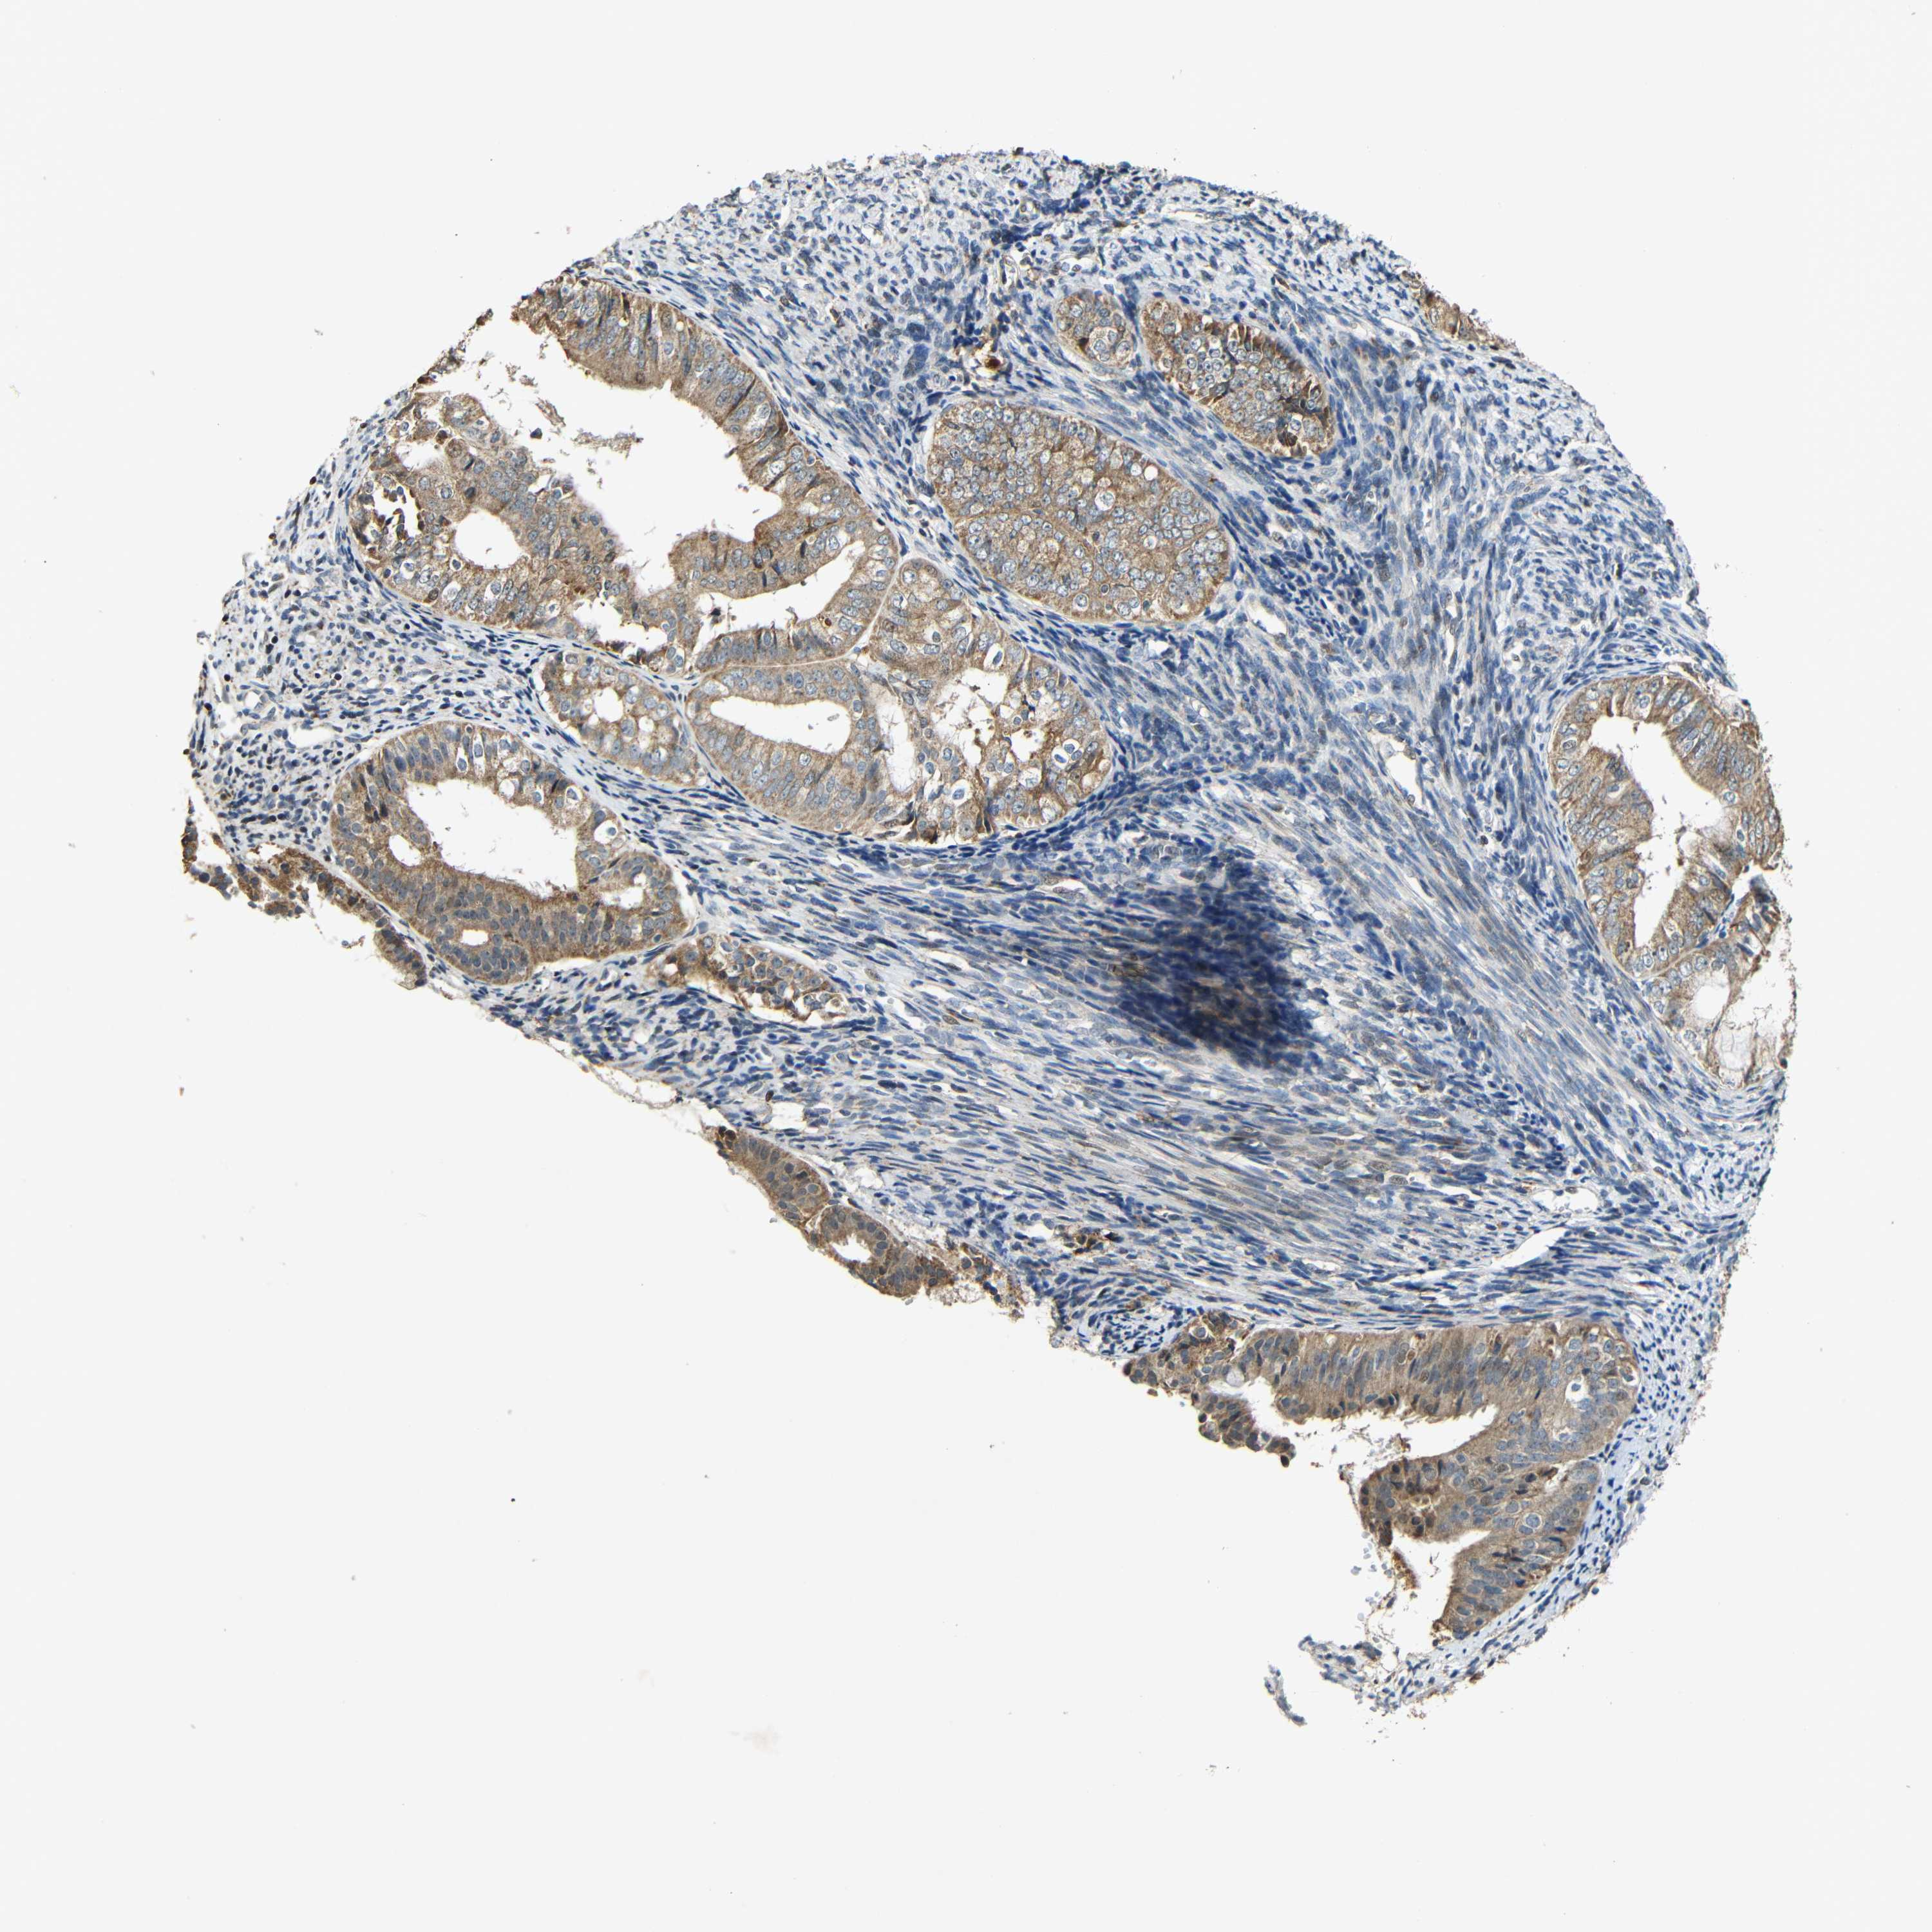

ENDOMETRIAL CANCER - Protein expressioni

A mouse-over function shows sample information and annotation data. Click on an image to view it in a full screen mode. Samples can be filtered based on level of antibody staining by selecting one or several of the following categories: high, medium, low and not detected. The assay and annotation is described here.

Note that samples used for immunohistochemistry by the Human Protein Atlas do not correspond to samples in the TCGA dataset.

Antibody stainingi

Antibody staining in the annotated cell types in the current human tissue is reported as not detected, low, medium, or high, based on conventional immunohistochemistry profiling in selected tissues. This score is based on the combination of the staining intensity and fraction of stained cells.

Each image is clickable and will lead to virtual microscopy that enables deeper exploration of all samples and also displays staining intensity scores, fraction scores and subcellular localization as well as patient and tissue information for each sample.

Antibody HPA011800

Staining

High

Medium

Low

Not detected

Intensity

Strong

Moderate

Weak

Negative

Quantity

>75%

75%-25%

<25%

None

Location

Nuclear

Cytoplasmic/membranous

Cytoplasmic/membranous,nuclear

Adenocarcinoma, NOS